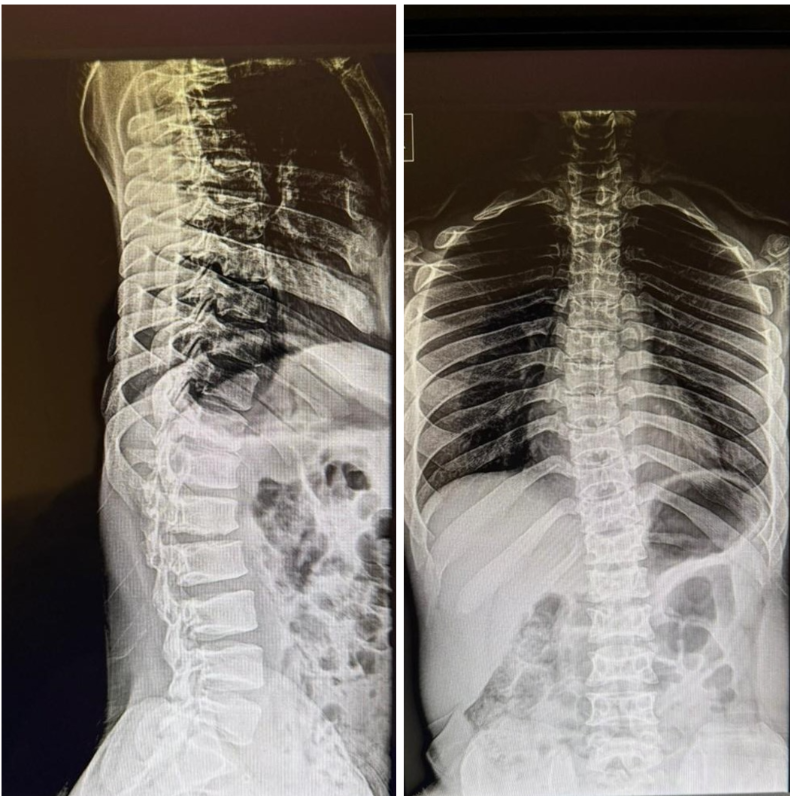

The post-operative course was uneventful. Rehabilitation was initiated on post-operative day 3. At 1-month follow-up, the patient reported significant improvement in leg pain, although some residual back pain persisted. At the 2-year follow-up, bilateral EHL strength had improved to 4/5, and functional mobility was maintained (Fig. 5).

Figure 5: Two-year follow-up standing whole spine radiograph shows no evidence of progressive thoracolumbar kyphosis.